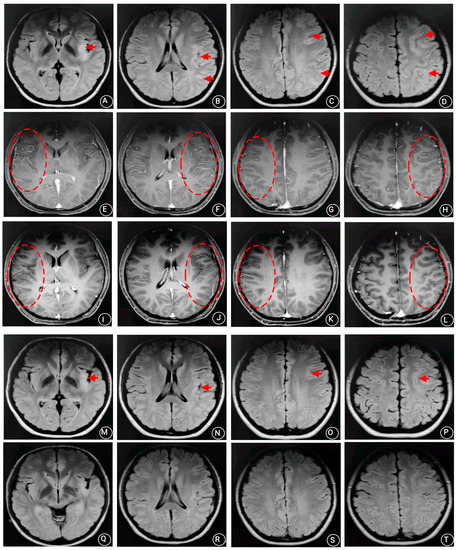

2. Case Presentation